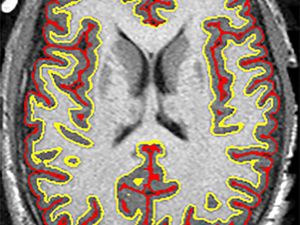

Brain scans revealed a striking difference between trial patients given the drug ibudilast and those who took an inactive placebo.

Every six months, the participants underwent magnetic resonance imaging (MRI) brain scans.